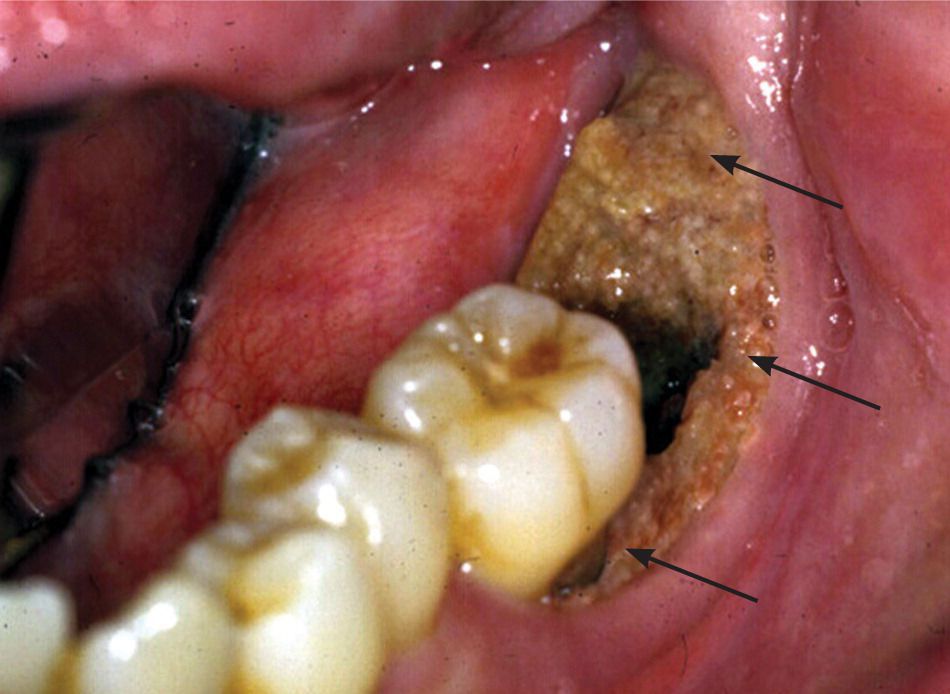

Osteonecrosis of the jaw is characterized by necrotic bone in the mandible or maxilla that occurs after tooth extraction. Risk factors include high doses of bisphosphonates, cancer, diabetes, and infections. Patients must pay attention to good oral hygiene.